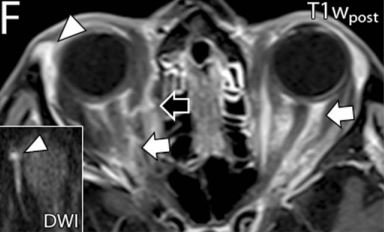

Intraorbital Findings in Giant Cell Arteritis on Black Blood MRI (Nov 2022)

This multicenter study examines orbital MRI findings using black blood (vessel wall) MRI in patients with Giant Cell Arteritis. Figure shows enhancement of the ophthalmic artery using VW-MRI (arrows).

Ophthalmic Artery Vessel Wall Inflammation in a Patient With Giant Cell Arteritis Presenting With Vision Loss (Mar 2024)

We report scalp and orbital MR findings in a patient with giant cell arteritis with inflammation of the temporal and ophthalmic arteries.

Orbital magnetic resonance imaging of giant cell arteritis with ocular manifestations: a systematic review and individual participant data meta-analysis (May 2023)

We systematically review all orbital MRI findings of patients with biopsy-proven GCA and visual disturbances. We report the clinical/exam findings and prevalence of orbital imaging findings in this disease.